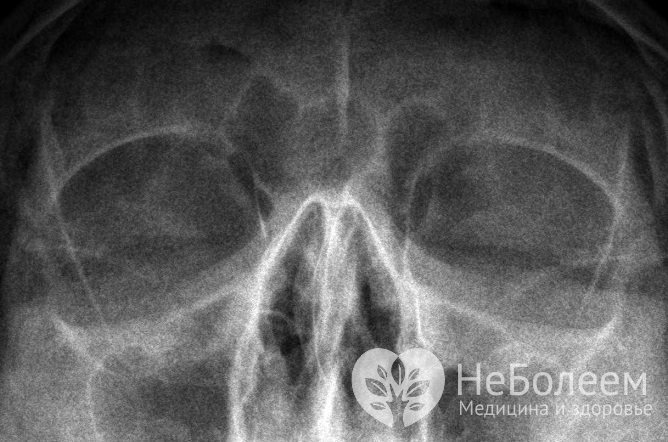

Вазомоторный ринит дифференцируют с аллергическим насморком, синуситом, туберкулезом, склеромой, сифилисом и гранулематозом Вегенера. Для уточнения диагноза обычно назначают рентгенографию придаточных пазух, общий анализ крови и аллергологические пробы. При нейровегетативном рините уровень эозинофилов и иммуноглобулинов класса Е (IgE) остается в пределах формы, кожные пробы дают отрицательный результат. При аллергической форме отмечается эозинофилия и повышенный уровень IgE сыворотки крови, при проведении кожных проб, как правило, удается выявить аллергены. У беременных женщин также определяется исходный вегетативный тонус и гормональный статус организма; особое значение имеют показатели эстрадиола, эстриола и прогестерона – гормонов, оказывающих влияние на нейровегетативные реакции.

Чтобы дифференцировать вазомоторный ринит с другими патологиями ЛОР-органов, проводят рентгенографию придаточных пазух носаПо показаниям проводятся дополнительные исследования – ринопневмометрия и эндоскопическое исследование носовой полости, микроскопия образцов эпителия слизистых оболочек и бакпосев слизистых выделений из носа.